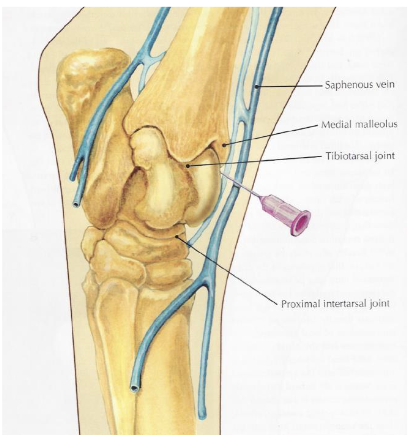

joints of the tarsus

red- tibiotarsal (or tarsocrural)

green- proximal intertarsal

blue- distal intertarsal

purple- tarsometatarsal

which joints of the tarsus communicate w/ e/o

tibiotarsal and proximal intertarsal joints

what is desensitized in a tibiotarsal joint block (dont hit saphenous vein)

tibiotarsal joint & proximal intertarsal joint (communicate w/ e/o)